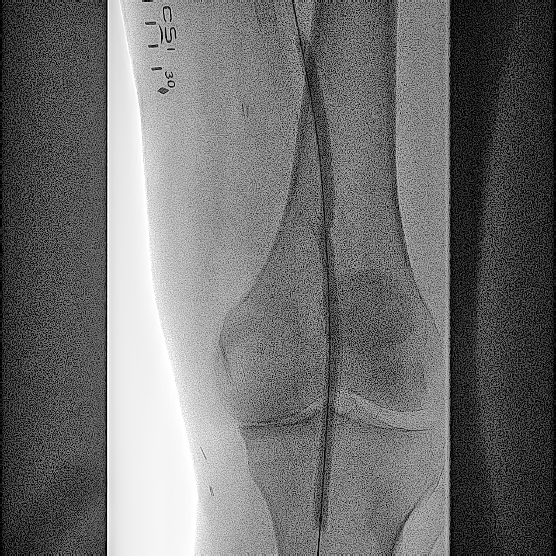

A 76-year-old White man with a medical history of hypertension, tobacco abuse, coronary artery disease, and coronary artery bypass grafting presented with a nonhealing wound of his left lower extremity. He had a previous history of stenting of the left superficial femoral artery (SFA) 8 years prior to presentation. He was noted to have complete occlusion of the left SFA and also abrupt occlusion of the left common and profunda femoral artery (Figure 1). The patient was offered an above-knee amputation, which he refused, and opted for endovascular intervention for revascularization of his entire left lower extremity.